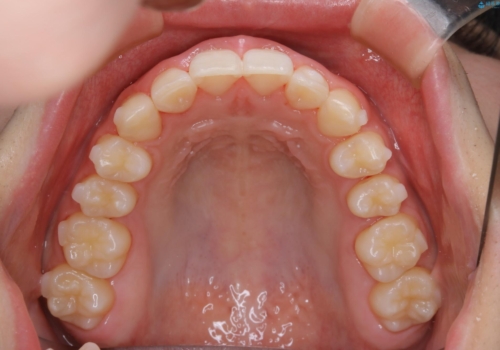

前歯のがたつきとディープバイト:インビザライン治療

- 前歯のがたつきと、噛み合わせが深いことを気にされてご相談にいらした方です。

インビザラインにて治療を行いました。

一般的に、歯冠(歯の長さ)が短い方はインビザライン治療に時間がかかりやすい傾向にあります。

歯の移動量に対して大きなブラックトライアングルもできることなく綺麗に並べることができ、大変喜んでいただけました。